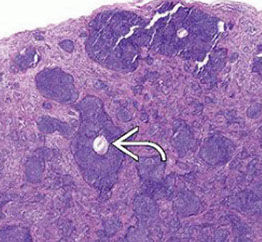

Pilomatrixoma

Trichohyaline granule (which are usually seen in hair shafts) in a pilomatrixoma

- aka calcifying epithelioma of Malherbe

solitary, bluish, firm (often calcifies), benign subepidermal spherical nodule

b9 hair follicle tumor

MC on face of kids or young adults

- 75% of childhood adnexal tumors

- can have multiple lesions in myotonic dystrophy

Sharply circumscribed cyst-like structure in dermis, possibly contiguous with hair follicle (may arise from hair matrix)

- can have inc mits (the malignant form is rare and usually very atypical)

- may have trichohyaline granules (which are usually seen in hair shafts)

3 cell types in fragmented cyst wall:

1) outer layer of blue (basophilic) basaloid martical cells with round nuclei and scant cytoplasm which dies and become dead keratin, which are the ghost cells

- imitate the cells in the root, or bulb of a normal hair follicle

2) mixed zone of eosinophilic cells c large round vesiculated nuclei

3) central zone sheets of keratinized pink "ghost" or "shadow" cells c distinct cell borders and central unstained nuclei

- difference from BCC: basaloid cells undergo abrupt keratinization and form "ghost" cells

Has foci of foreign body reaction, calcifications and ossification in shadow cell lobules

See melanin in shadow cells

Fibrotic stroma infiltrated with granulomatous inflam

Solid nests of basaloid cells may cause misdiagnosis of BCC

Ddx: Basal cell carcinoma c matrical differentiation (differs by continuity with epidermis and abrupt transition into shadow cells without the eosinophilic zone)